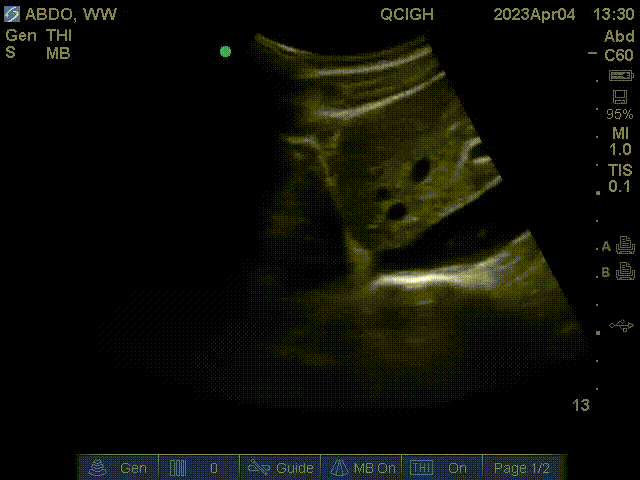

Gallbladder

The gallbladder is visualized in this scan at the center of the image. In addition, the portal vein is the circular struction with a hyperechoic wall left of the gallbladder in this scan. The inferior vena cava is the cylindrical structure right of the liver.